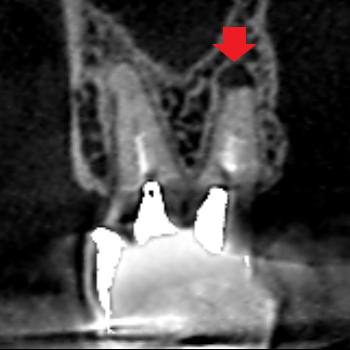

上顎第二大臼歯の口蓋根の矢状断のCT画像です。

矢印の上顎第二大臼歯の口蓋根の先に膿の影がみられます。